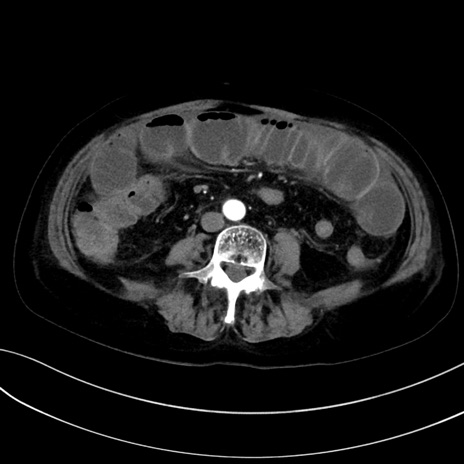

症例13 CT(横断像)1日半後